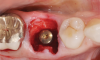

(3.) This series of clinical images illustrates the use of an implant with well-defi ned

threads that improve lateral bone engagement. In a multirooted extraction socket where there are large voids, this can help to achieve initial implant stability.

Figure 3